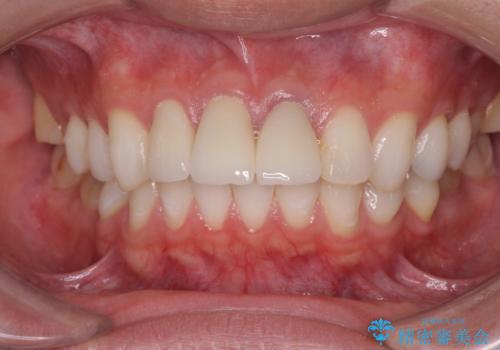

- 50.6万円(ジルコニアクラウン×3・仮歯×3・歯の挺出&歯周外科)費用は治療当時の料金となります

歯の挺出を行ったことで歯ぐきの腫れも改善され、安定した歯周環境下でのセラミッククラウン治療を行うことができました。